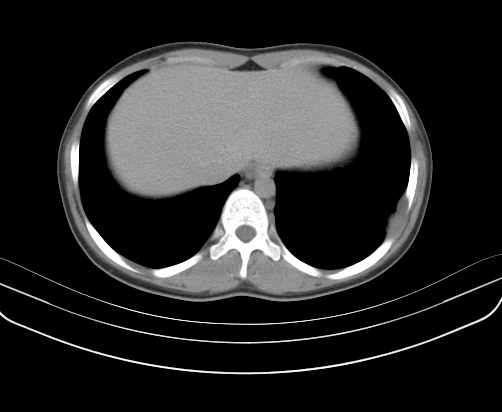

胸部